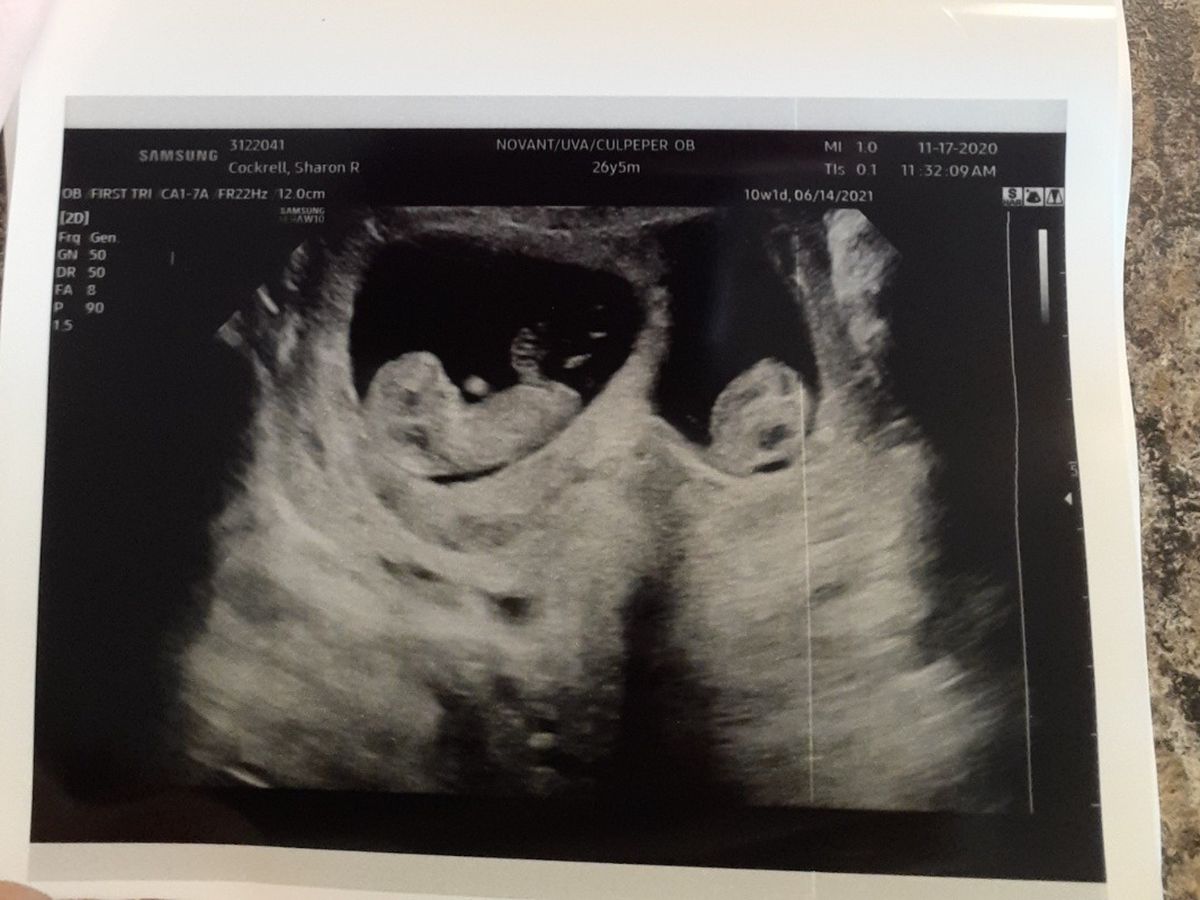

James and I were shocked and a little terrified when we found out we were having twins but it's been such an unexpected blessing.

Welcome to the world, Finneas Anderson Van Cleave and Theodore James Van Cleave.